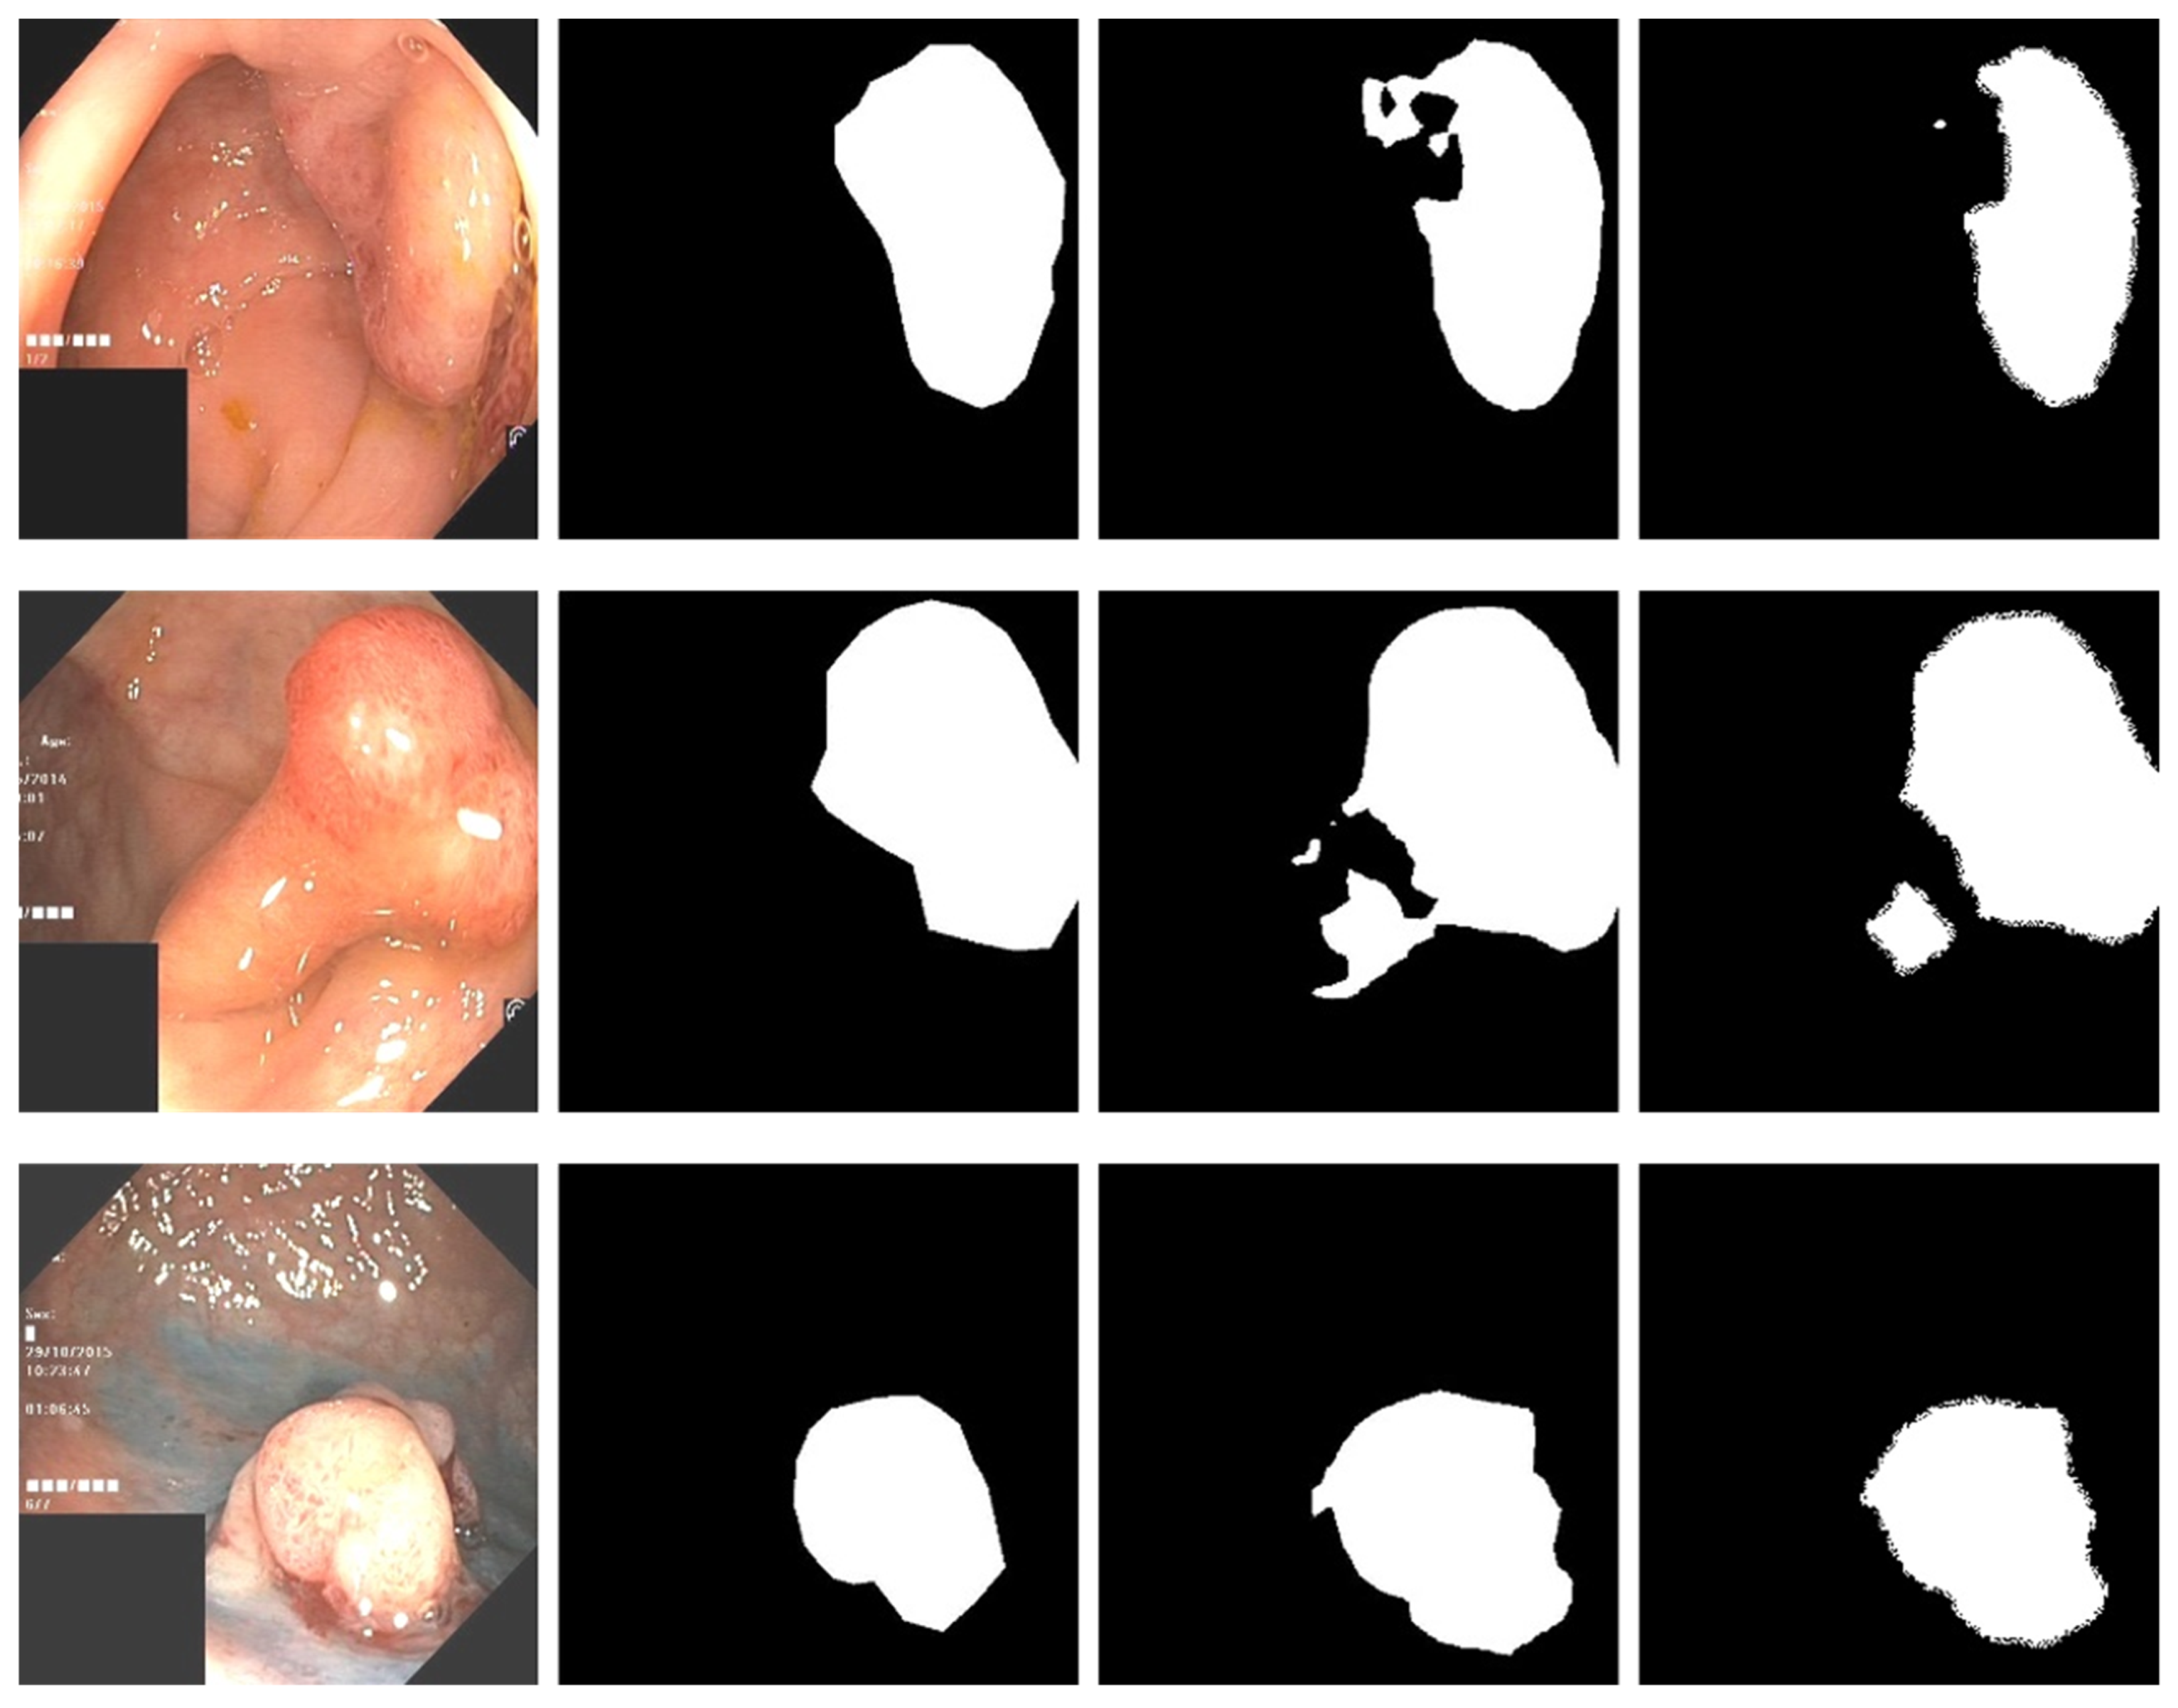

Figure 5 is a comparison of the direct prediction map of the model and the conditional random field after refining the boundary. A conditional random field can effectively fine-tune the boundary of a segmented image. In our work, a high-density conditional random field was applied to the experiment.

Figure 5. The first column is the original input image, the second column is the mask map, the third column is the direct prediction map of the model, and the fourth column is the prediction map with the conditional random field added.